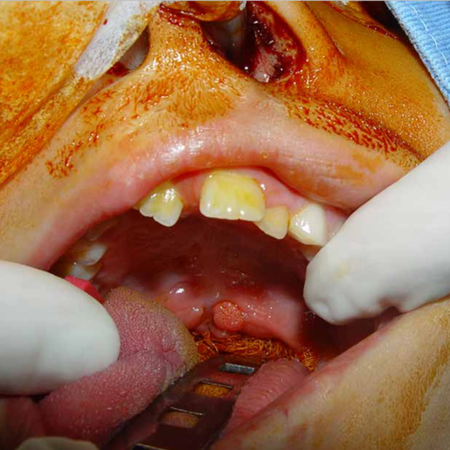

Solid variant of aneurysmal bone cyst in mandible: a case report

Introduction: The Aneurysmal Bone Cyst (ABC) is a rare, benign, and locally aggressive lesion that may present a solid variant. Its differential diagnosis can include both benign and malignant lesions. Case Report: This report details the case of a 57-year-old male presenting with pain and swelling in the right mandibular angle, diagnosed with the solid variant of an aneurysmal bone cyst. Surgical planning incorporated 3D printing of a biomodel for pre-molding of the reconstruction plate....